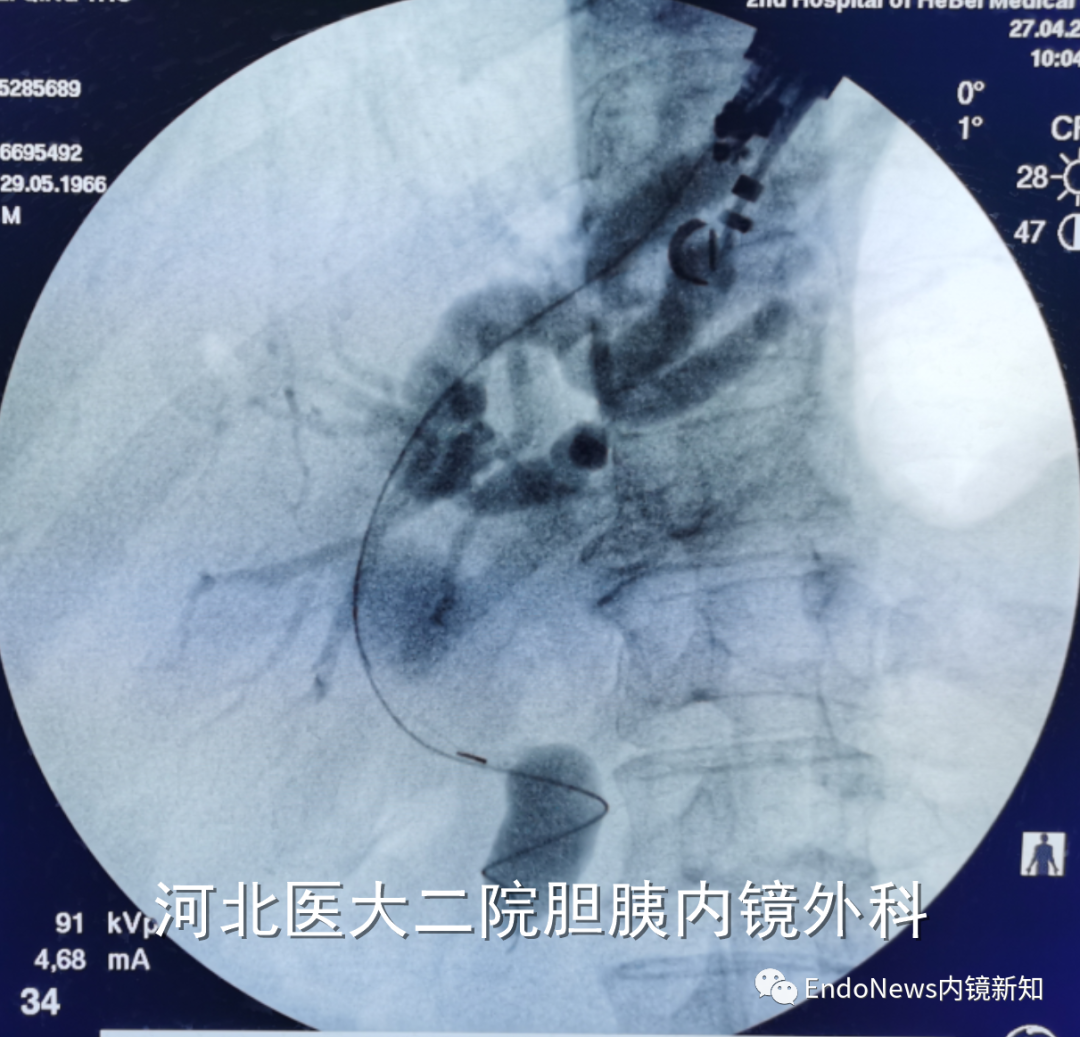

如下图所示,肝门胆管狭窄(Bismuth IV型),导丝进入肝右叶胆管后就可以置入支架引流肝右叶胆管:

取石网篮 为什么贵EUS-BD操作中的细节:导丝如何超选?_https://www.jmylbn.com_新闻资讯_第14张

取石网篮 为什么贵EUS-BD操作中的细节:导丝如何超选?_https://www.jmylbn.com_新闻资讯_第15张